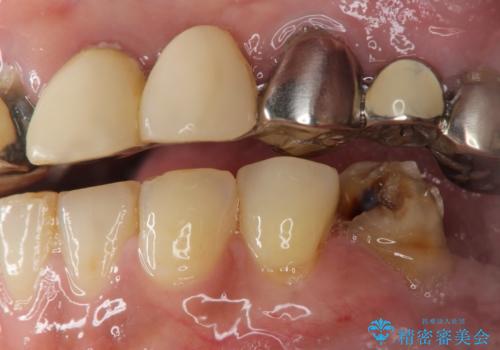

痛くて噛めない インプラントで全て治療したい

- 痛くて噛めない、これまでだましだまし治療をしてきたがこれを機にすべてきっちりと治したい、口の中の悩みを解決したいと来院されました。

抜歯や歯周病治療、欠損補綴を含め、全顎的な治療を計画・提案します。